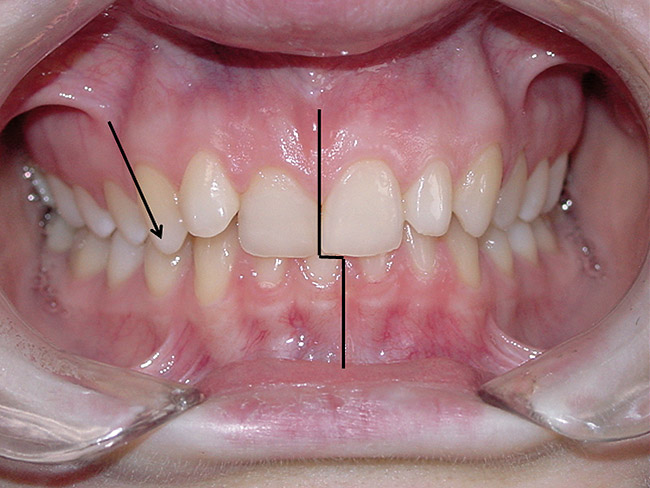

If the maxillary anterior teeth are positioned or inclined palatally, upon closure the lower teeth are going to first contact these teeth, which will force the mandible to shift to close into a retruded position. The objective is to try to identify this shift from primary contact to closure. This type of fence could potentially lead to shifting of the maxillary anterior teeth, breaking of the teeth, and/or muscular and jaw dysfunction as a result of posterior displacement of the mandible (Figure 2, Figure 3, Figure 4 and Figure 5).

Figure 2  The relative entrapment of the mandible from the retroinclination of the upper incisors.

Figure 3  The relative entrapment of the mandible from the retroinclination of the upper incisors.

Figure 4  Palatally inclined upper central incisors  indicating a negative torque. In this situation the first  point of contact upon closure occurs in these teeth  leading (Occlusal Fence I) to a posterior shift and  distalization of the mandible.

Figure 5  After orthodontic correction, the upper  central incisors have a positive torque, and the posterior  shift of the mandible on closure is eliminated.

Figure 6  The inclination of the canines provide  the midline position of the mandible. When these  teeth are inclined (eg, the right canine in this  case), they tend to shift the mandible away from  the midline (in this case toward the left).